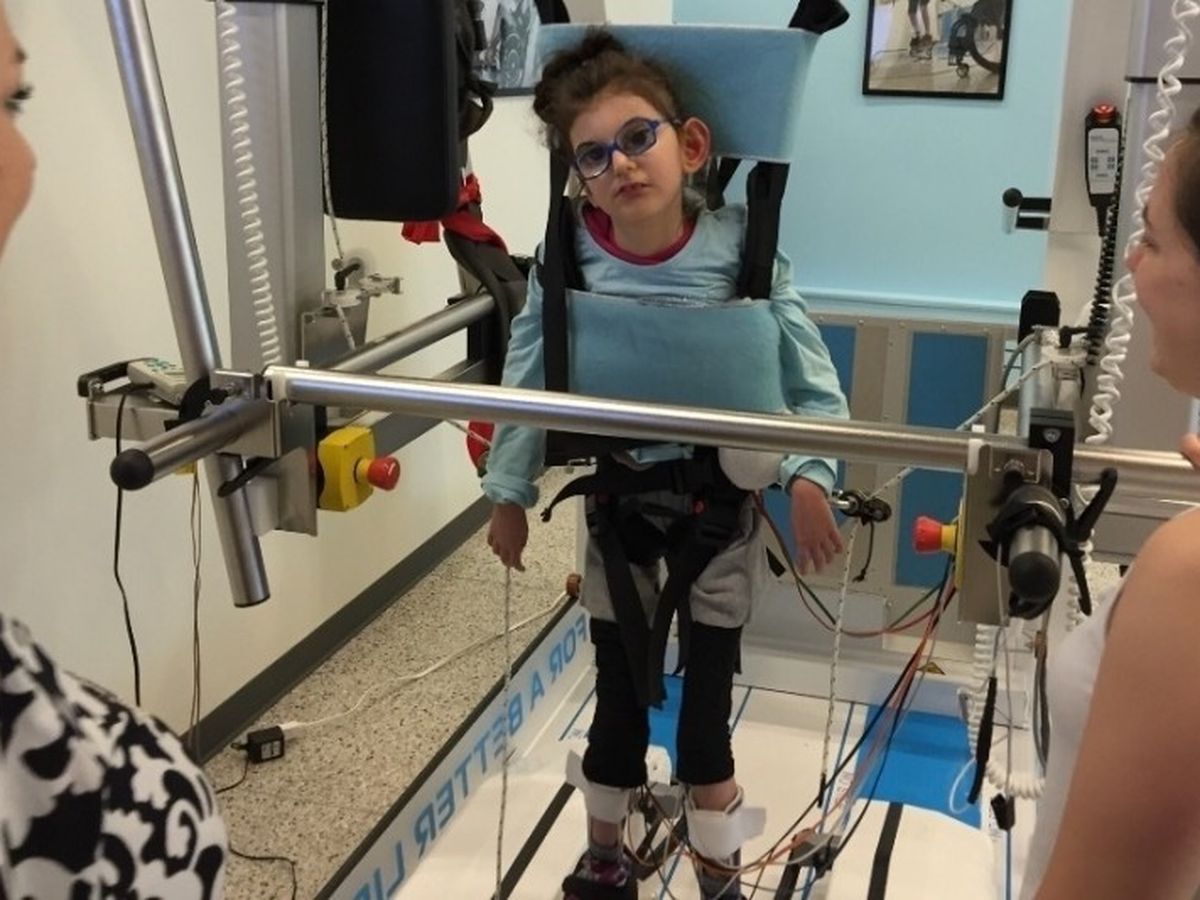

My name is Judit and this is my little girl Ariana. She was born with health problems and had many surgeries.

Right now she is 10, about 15kg (35lbs). She is beautiful, funny, and working hard every day to achieve wellness. She is homeschooled and can read hundreds of words and can count in the 1000's. She's very intelligent and started to use a facilitated communication board and choice board to tell me what she wants as she can't speak yet.

Physically she is behind, can't sit or walk, buy I am working on

building her up from zero neurologically and physically.

One of our many, but pressing problems is her osteoporosis and serious scoliosis which is putting pressure on her heart and lungs. She might need spinal surgery but it's not easy in her case.